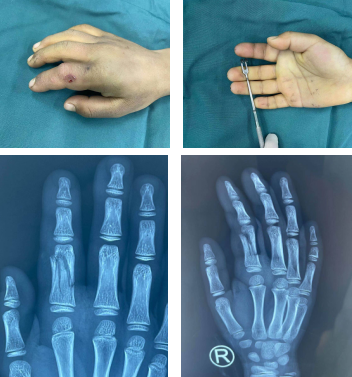

一周前,9岁的男孩阳阳(化名)因在家中玩耍时不小心摔倒被桌子砸伤右示指,导致右示指肿胀严重、无法活动,父母赶紧带来我院就诊。熊祖国医师接诊后,经过查体与相关辅助检查,确诊为:右示指近节粉碎性骨折,指体伴有一定程度的旋转畸形。

术前

确定下来手术方案后,熊祖国医师为阳阳安排了手术,术中予闭合复位、矫正旋转畸形之后,克氏针打入内固定骨折端,术后无手术疤痕,手术非常成功,骨折复位良好。

术中